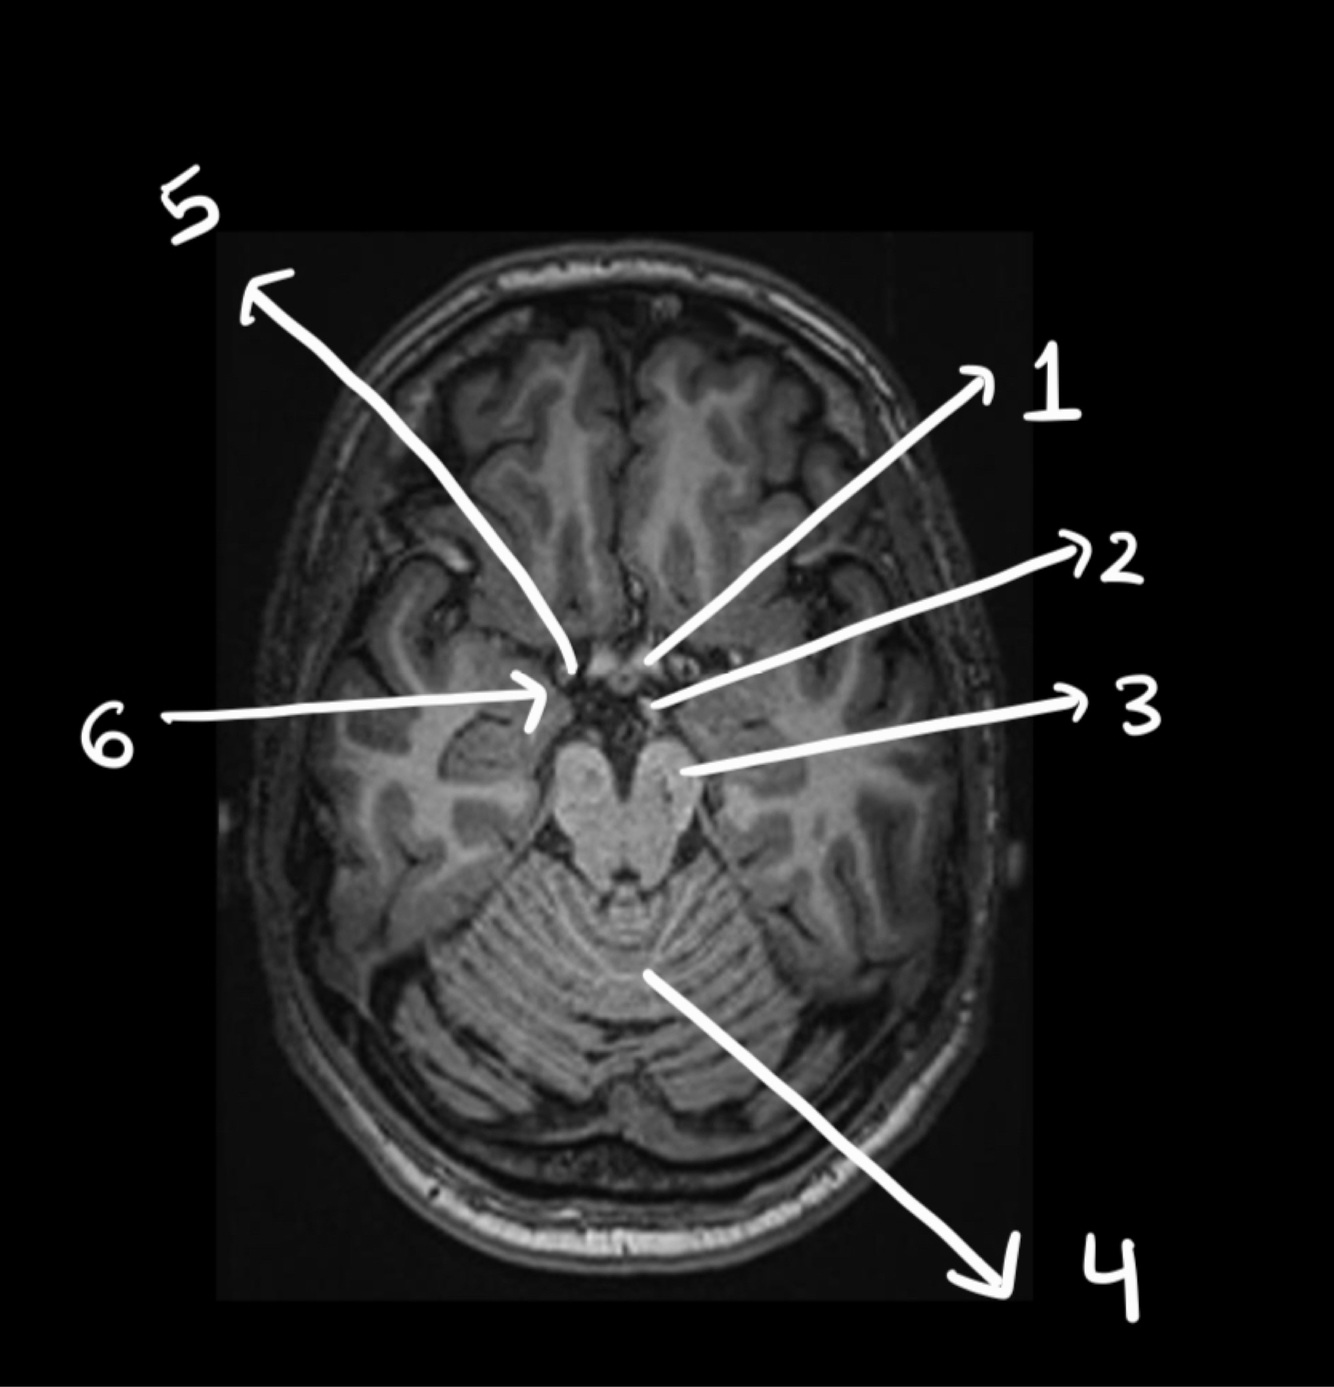

Name the structure

Hypophisis

29

30

4th ventricle